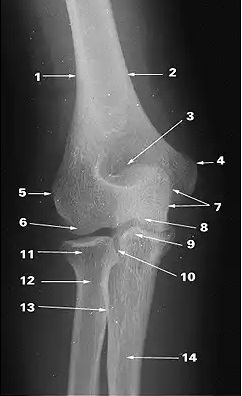

What does 1 indicate?

pisiform

What does 2 indicate?

triquetrum

What does 3 indicate?

hook of hamate

What does 4 indicate?

capitate

What does 5 indicate?

scaphoid

What does 6 indicate?

trapezium

What does 7 indicate?

ulna

What does 8 indicate?

radius

medial supracondylar ridge

lateral supracondylar ridge

capitulum

olecranon fossa

trochlea

What does 9 indicate?

coronoid process of ulna

medial epicondyle

lateral epicondyle

What does 10 indicate?

proximal radioulnar joint

olecranon